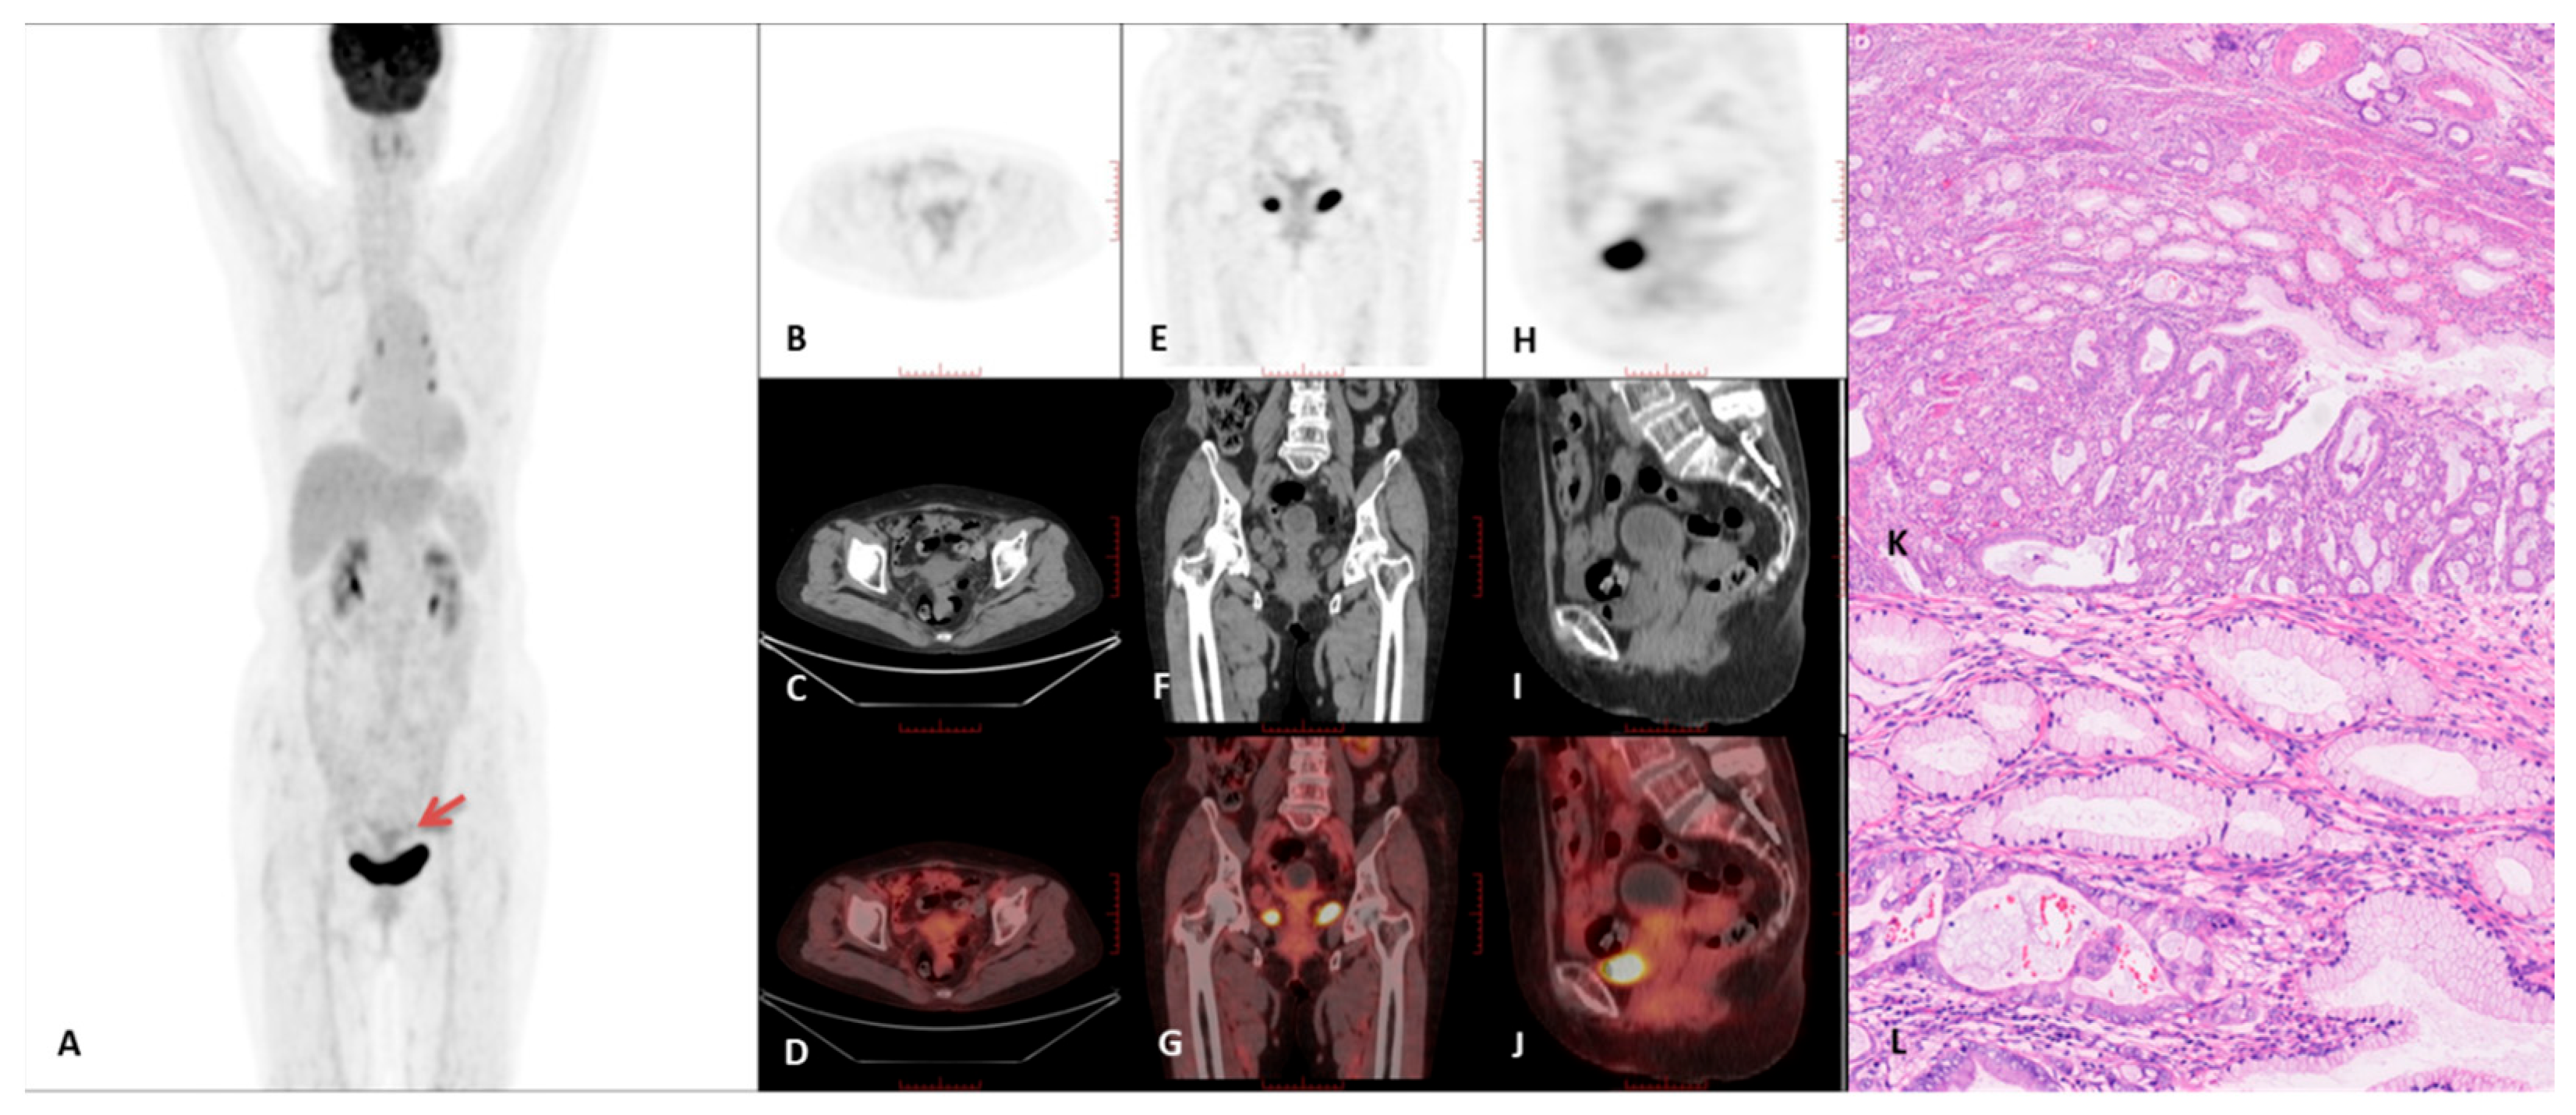

3.2. PET/CT Imaging Characteristics

| Growth pattern | <0.001 | <0.001 | |||

| Mass forming | 1 | 37 | 24 | ||

| Diffuse infiltration | 11 | 11 | 6 | ||

| Intrauterine fluid | <0.001 | 0.0024 | |||

| Present | 11 | 11 | 12 | ||

| Absent | 1 | 37 | 18 | ||

| Cyst | <0.001 | <0.001 | |||

| Microcyst | 1 | 0 | 0 | ||

| Macrocyst | 11 | 9 | 9 | ||

| None | 0 | 39 | 21 | ||

| SUVmax | 7.5 ± 3.8 | 17.4 ± 6.7 | 19.1 ± 11.4 | <0.001 | <0.001 |

| T/L SUVmax | 2.5 ± 1.6 | 5.5 ± 2.6 | 5.7 ± 3.4 | <0.001 | <0.001 |

| Case # | FIGO 2018 | Tumor Diameter Mean Value (cm) | Macrocysts | Tumor Growth Pattern | Intrauterine Fluid | SUVmax | T/L SUVmax |

|---|---|---|---|---|---|---|---|

| 1 | IVB | 2.9 | Present | Diffuse | Present | 3.0 | 1.0 |

| 2 | IVA | 2.4 | Present | Diffuse | Present | 2.8 | 1.1 |

| 3 | IB | 3.7 | Present | Diffuse | Present | 2.6 | 0.8 |

| 4 | IVB | 6.5 | Present | Diffuse | Present | 9.3 | 3.9 |

| 5 | IVB | 3.3 | Present | Mass | Present | 9.7 | 2.7 |

| 6 | IIIC | 4.8 | Present | Diffuse | Present | 11.6 | 3.1 |

| 7 | IIA | 4.6 | Present | Diffuse | Present | 6.8 | 1.7 |

| 8 | IVB | 2.9 | Present | Diffuse | Present | 12.6 | 3.8 |

| 9 | IVB | 5.2 | Microcysts | Diffuse | Present | 6.2 | 1.9 |

| 10 | IVB | 5.9 | Present | Diffuse | Absent | 13.3 | 6.0 |

| 11 | IVB | 6.8 | Present | Diffuse | Present | 7.7 | 3.1 |

| 12 | IVB | 3.7 | Present | Diffuse | Present | 4.5 | 1.2 |